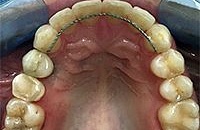

Работы врача